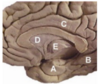

Label 5, 6 & 7

1 - superior temporal gyrus;

2 - inferior frontal gyrus; 3 - insular cortex;

4 - temporal stem;

5 - internal capsule;

6 - thalamus;

7 - lentiform nucleus (the internal and external globus pallidus and the putamen)

8 - frontal horn;

9 - superior circular sulcus;

10 - inferior circular sulcus.